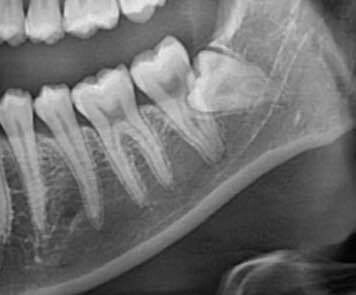

매복 사랑니 발치

매복 사랑니가 위험한 이유

비정상 각도·방향 → 옆 어금니 손상·충치

잇몸 염증·심한 통증 → 부기·발열·개구 장애

신경관 근접 → 방치 시 감각 이상 위험

3. 신경 손상 최소화를 위한 정밀 진단 및 계획

3D CT를 활용한 정밀 진단: 발치 부위의 뼈 구조, 사랑니 뿌리의 형태, 신경관과의 거리 및 위치 등을 3차원적으로 정확하게 파악하여 신경 손상 가능성을 미리 예측하고 대비합니다.

개별 맞춤 발치 계획 수립: 정밀 진단 결과를 바탕으로 각 환자분의 케이스에 최적화된 발치 계획을 수립하고, 신경관의 위치를 고려한 안전한 각도와 방법으로 시술을 진행합니다.

숙련된 의료진의 섬세한 시술: 다년간의 경험과 숙련된 기술로 신경 구조물을 피해 안전하게 사랑니를 분리하고 발치합니다.